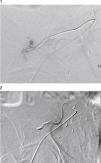

A urologist was consulted owing to suspected active bleeding. The urologist believed that the patient was at high risk of a transplantectomy if surgery was performed, and so it was decided to perform a diagnostic arteriogram with the possibility of embolisation of the bleeding point. Selective renal artery catheterisation was performed through the femoral approach, up to the area of contrast extravasation, with an image suggestive of an AVF, and embolisation of 2 distal branches was performed (Figs. 1 and 2). Afterwards, a urologist drained the parenchymal haematoma of the upper pole and placed haemostatic material. After clinical stabilisation, he required haemodialysis and multiple blood transfusions, and started effective diuresis with improvement in his glomerular filtration rate. A year later, the patient remains stable and has preserved his renal function.

In our case, the size of the haematoma, the late symptoms (third day) and the drop in haemoglobin, although the patient's haemodynamics were not affected and were perhaps sustained through hyperreninaemia, suggested the possibility of persistent bleeding. As a result, prior action by an angioradiologist, before the surgical procedure, was proposed. After the active bleeding point was identified and embolised, the patient underwent urological surgery in which the haematoma was drained and diuresis and renal function were recovered.